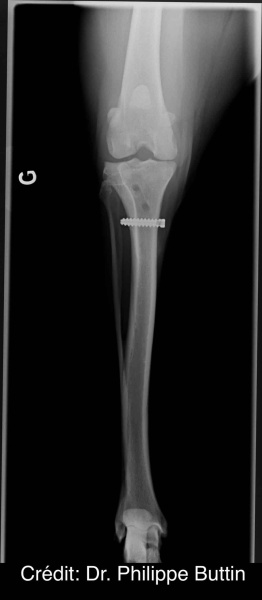

Radiologické snímky